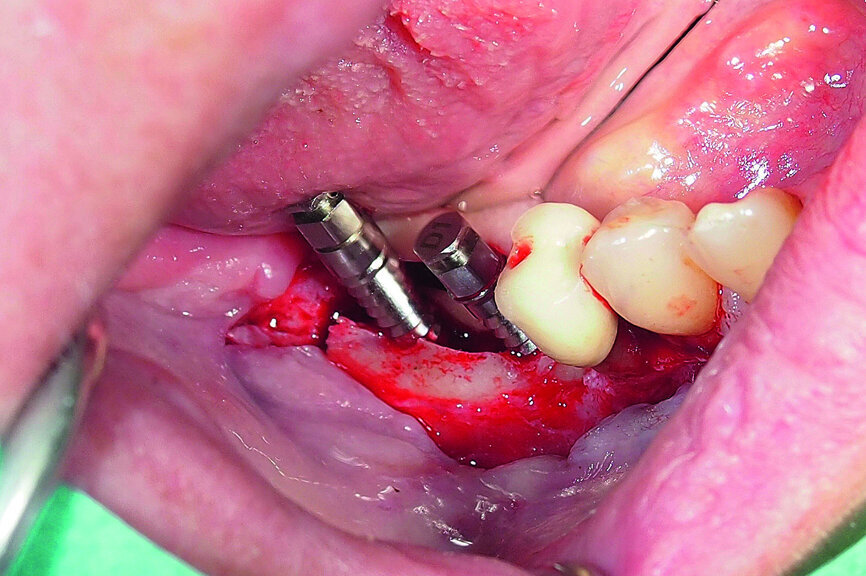

Fig. 18: Placement of two GC Aadva Standard implants with regard to the future restorative margins.

A demonstration of this technique is shown in Figures 13 to 20. This case presents an elderly woman who had lost her teeth in the lateral mandible decades ago. Being a healthy non-smoker with good oral hygiene, no history of periodontal disease and low masticatory forces, she was an adequate candidate for bone grafting together with implant placement. The future restorative margins allowed the usage of ridge splitting (Figs. 13 & 14). Therefore, we opted for a ridge split with vertical releases carried out utilising a partial-thickness flap. The periosteum was left attached in order not to impede the perfusion of the buccal plate (Fig. 15). After ridge splitting, the buccal and lingual plates were separated with the use of bone spreaders (Split-Control Plus, Meisinger) to allow the placement of two GC Aadva Standard implants, one of 3.3 mm in diameter and 8.0 mm in length and the other measuring 4.0 mm in diameter and 8.0 mm in length (Figs. 16–18).